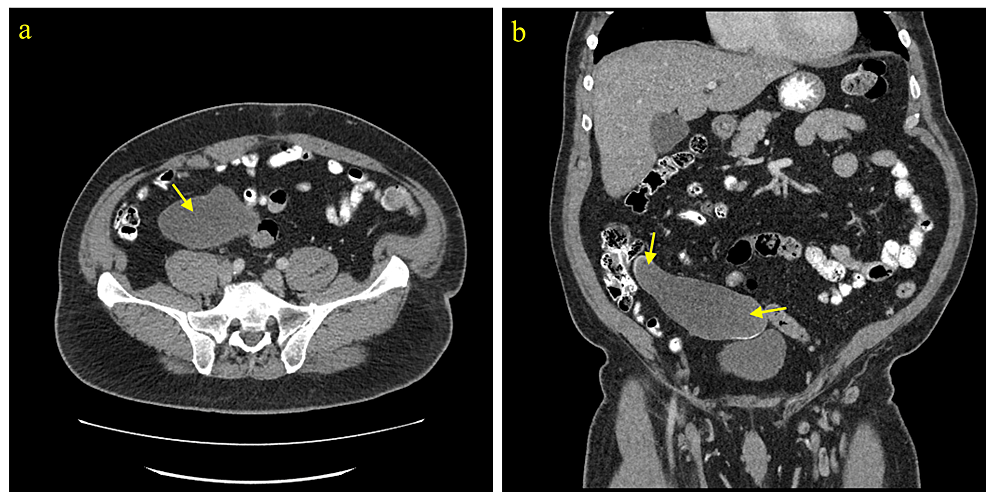

Although LAMN can be generally asymptomatic and stable, it can also lead to a number of serious complications over time [1-3]. LAMN can rupture and disseminate mucin and neoplastic cells into the peritoneal cavity and result in PMP, an intraperitoneal accumulation of mucinous tumors and mucinous ascites that is associated with poor outcomes and high mortality risk [1-3]. Therefore, timely workup and management are essential to prevent progression to PMP and metastasis and improve overall outcome and recovery. Given it can be asymptomatic and have nonspecific findings when symptomatic, imaging is important for the initial detection of a mucinous appendix and surveillance for rupture. When intact, abdominal ultrasound can show a distended cystic appendix with porcelain wall calcification and a lamellated mucinous “onion-skin” appearance, though rupture will show an interruption in the appendiceal wall with leakage, while PMP will show thickening of the peritoneum or omentum, anechoic regions, echogenic foci, and septations [3]. CT can show an enlarged appendix with wall calcifications and thickening, and additionally demonstrate septations, calcified nodules, and liver margin scalloping in PMP (Figures 2–4) [1, 3]. Magnetic resonance imaging (MRI) can show a hyperintense distended appendix and bright mucin appearance on T2-weighted MRI, as well as nodularity on MRI with contrast [3]. A biopsy is not recommended due to perforation risk, though if the lesion has disseminated peritoneally, a biopsy of peritoneal nodules can be helpful for diagnosis [3]. Through these diagnostic measures, they can help to identify mucinous appendices, monitor for rupture, and allow for timely management to reduce the risk of dissemination and progression to PMP.